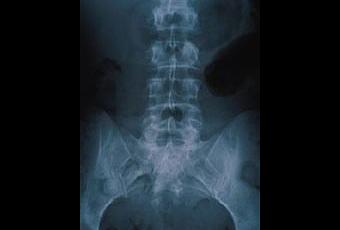

Après 3/4 semaines de chômage, le bilan n'est pas fameux en termes de KPI, pourtant j'avais la motivation au départ, mais le système sanguin ralenti de mon ancien employeur, la façon dont ça s'est passé, et les contrariétés personnelles induites n'ont pas aidé à clore l'affaire et booster mon moral (toujours balancer la faute sur quelqu'un d'autre, c'est très important !). Par ailleurs j'ai cette terrible propension à bordéliser toute ma créativité qui fait qu'aujourd'hui je ne sais plus ce que je veux faire en vrai de vrai : partir ou rester, l'espagnol ou le macramé, la comm' ou le bâtiment, petits-pois ou carottes, bière ou vin (rhaaaa cruel dilemme !!!), jeans ou robe, péniche ou roulotte, travailler ou glander... Cette chouette incapacité à faire des choix m'emmène sur la pente savoneuse de l'interrogation perpétuelle qui fait se pointer mon pire ennemi (avec l'insomnie, mais ça c'est pour un autre post), à qui j'ai déjà fait sa race pourtant :

la sciatique.

Sciatique mon amie, tu me lamines les jambes, devant, derrière, je suis complètement droguée par ta faute, accro aux myorelaxants... Je dors 5 heures d'affilée l'après-midi ratant par la même occasion, la saison 3 (ou 4) de Grey's Anatomy (diffusée sur TF1 à 17h) et le film catastrophe de 15h.

Sciatique mon amie, je te propose d'aller squatter chez quelqu'un d'autre, là tu m'as complètement vidée, paralysée, et maintenant j'ai envie à nouveau d'avoir l'air d'équerre et jolie (avec mon nouveau sac rose - je vous ai dit pour le sac rose ?). Si t'allais par exemple chez le grand escogriffe, mal gaulé comme il est ça doit pas être bien compliqué de te le faire non ? Comme ça je peux reprendre une activité normale, arrêter d'annuler plein de trucs et rebrancher ma machine à coudre pour faire des poupées vaudou. Allé, s'te plait, casse toi tu pues !